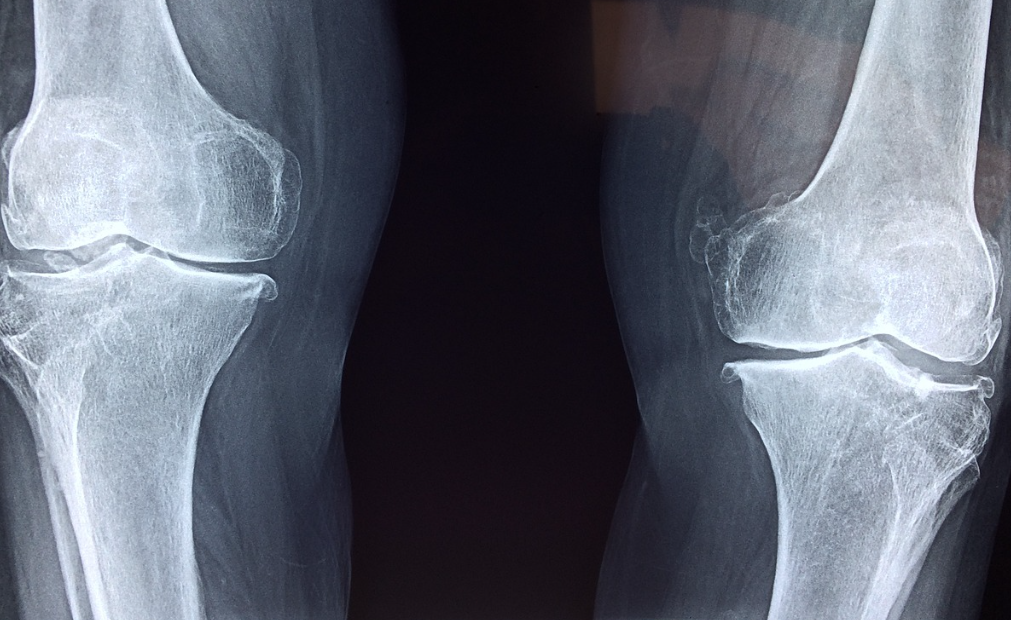

🏥 4. 정기적인 골밀도 검사 받기

골다공증은 조기에 발견할수록 관리가 쉽습니다.

✅ 골밀도 검사가 필요한 대상

- 65세 이상 여성, 70세 이상 남성

- 폐경 후 65세 미만이지만 고위험 요소가 있는 여성

- 골다공증 가족력 또는 골절 경험이 있는 경우

골밀도 검사 후 골다공증이 진단되면, 개인의 상태에 맞는 치료가 필요합니다.